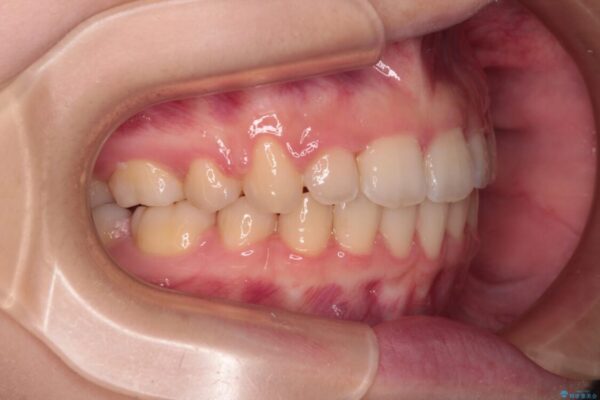

上下の前歯が突出しており、口が閉じにくいとのことで来院された患者様です。

上下前歯が著しく前突している状態であったので、上下左右の第1小臼歯4本を抜歯し、ワイヤー装置にて矯正治療を行うこととしました。

治療前

• 【モニター】口が閉じられない ワイヤー装置での抜歯矯正 治療前画像